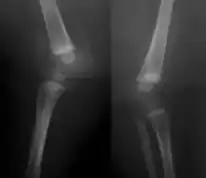

X-ray knees -